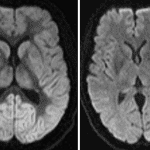

Indication: Post cardiac arrest

Findings

- Diffuse low ADC values throughout the bilateral cerebral cortical gray matter and subcortical white matter with an area of diffusion signal hyperintensity in the posterior left temporal lobe

- T2/FLAIR signal hyperintensity diffusely involving the bilateral basal ganglia, thalami, hippocampi, substantia nigra, periaqueductal gray matter, and the cerebellar vermis and hemispheres

- Generalized cerebral edema with compression of the fourth ventricle

- No evidence of acute hemorrhage, herniation, or hydrocephalus

Diagnosis

- Hypoxic ischemic encephalopathy (adult)

Findings consistent with severe hypoxic ischemic encephalopathy. Mass effect on the fourth ventricle without evidence of herniation or hydrocephalus. No acute hemorrhage.